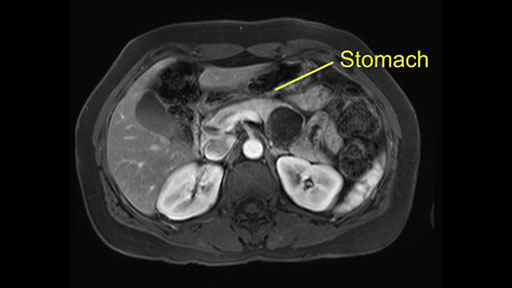

Anterior pancreas margin: posterior wall of stomach

In terms of maintenance of the regular planes, other factors that we need to consider is whether you need to enter in posteriorly to Gerota’s fascia to obtain an adequate margin and anteriorly to ensure the tumor can be mobilized safely off of the posterior wall of the stomach.

So first step that we do: mobilize the splenic flexure first to visualize Gerota’s fascia and that would help bring down the colon and expose the pancreatic tail. So now that the pancreas is visible, division of the gastrocolic ligament will come into view. And a window can be created at the inferior edge of the pancreas to slowly lift the inferior edge to expose the splenic vein behind. This is the slow-down moment that I am talking about because the MR shows that there could be contact with the cyst. It’s important to know that to avoid perforation, to avoid rupture of the cyst, because we need to avoid touching the cyst, it is quite a size of 4.3 about 4cm.